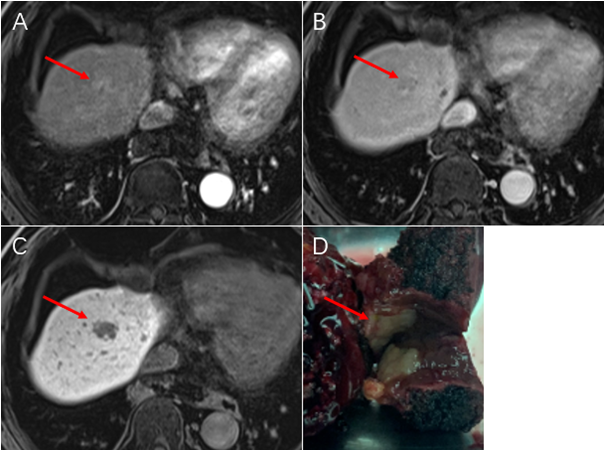

经过全面检查,小张诊断为早期肝癌。外科医生告知,由于肿瘤位置特殊,贴近大血管,属于手术困难部位。而且患者还年轻,此部位手术会对肝脏损伤较大,特请肿瘤放射治疗科医生进行会诊。

在充分了解情况后,肿瘤放射治疗科医生认同外科医生意见,建议采取少分次、大分割的立体定向放射治疗(SBRT)。经充分沟通后,小张接受了肿瘤放射治疗科医生的建议。

放射治疗后三个月复查,小张的肿瘤已经明显缩小;AFP也明显下降,接近正常。放疗后六个月复查,肿瘤已完全消失,AFP正常。现在小张定期来我院门诊随访复查,监测肿瘤的变化。